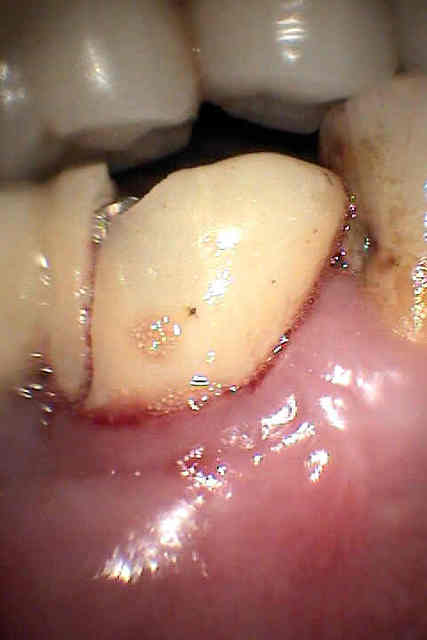

photos et radio de mauvaise qualité je n'avais pas mon matériel sous la main ce matin mais uniquement la caméra endobuccale que je ne manie que rarement (ca se voit),depuis un cambriolage je ne laisse plus rien de valeur facilement transportable .Mais j'ai pensé à ton sujet alors j'ai paré au plus pressé

Ce patient( proche de la famille) a été équipé site de 36 37 il y à deux ans et mis en provisoire à l'époque parti à 700 km du cabinet me contacte mardi en me disant qu'il revenait pour la toussaint mais qu'il avait un petit souci du coté droit....

et voilà le résultat : fracture des deux petites provisoires au niveau de l'extension mesiale ; voussure vestibulaire que l'on devine malgré la photo de mauvaise qualité .